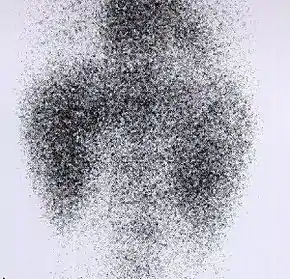

![]() Decreased Tc99m-DMSA uptake in both kidneys, suggestive of renal failure. | |

A DMSA scan is a radionuclide scan that uses dimercaptosuccinic acid (DMSA) in assessing renal morphology, structure and function. Radioactive technetium-99m is combined with DMSA and injected into a patient, followed by imaging with a gamma camera after 2-3 hours.[1] A DMSA scan is usually static imaging, while other radiotracers like DTPA and MAG3 are usually used for dynamic imaging to assess renal excretion.[2]